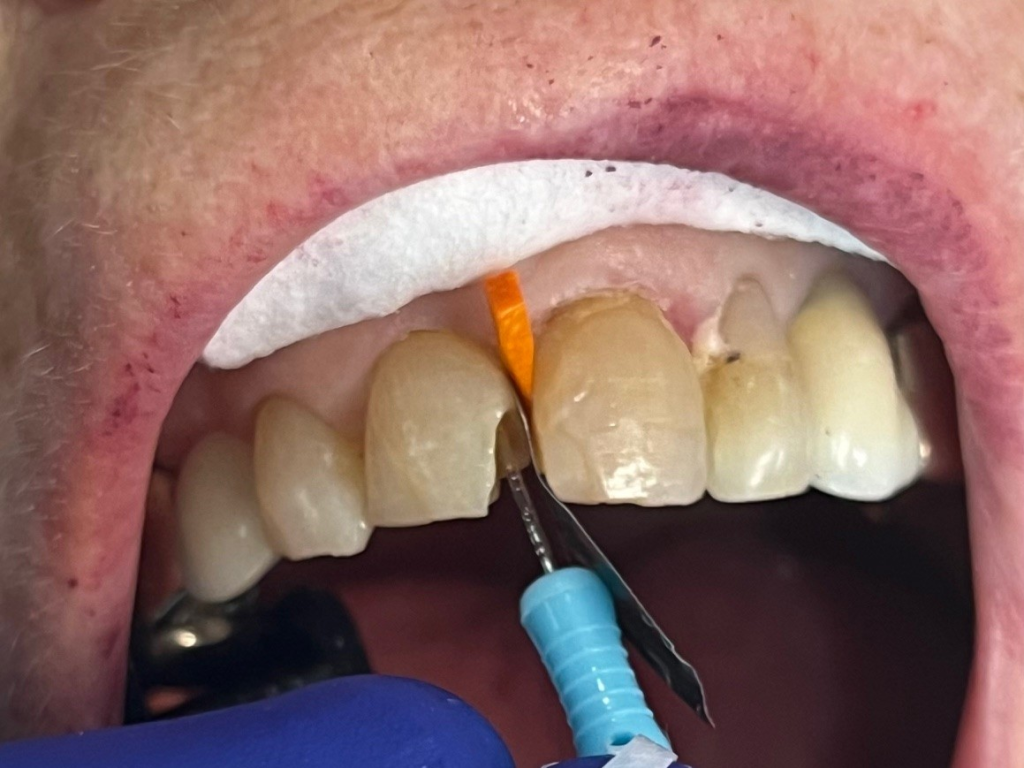

Anterior broken tooth. Double DentXpinTM repair.